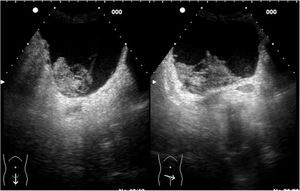

Ecográficamente las visualizamos como lesiones anecogénicas, redondeadas, de tamaño variable, de paredes finas y lisas, con refuerzo acústico posterior y sin contenido en su interior ni tabiques. Pueden ser corticales si dependen de la corteza renal o sinusales si se localizan en la zona medular10. Existen casos excepcionales en los que el quiste puede tener algún tabique en su interior, de mayor o menor grosor, con o sin contenido en su interior. Es en estas situaciones en las que hablamos de quistes complejos y es importante realizar una TAC para la correcta clasificación del quiste en la conocida como clasificación de Bosniak, que realmente es una clasificación radiológica de la TAC, no es una clasificación ecográfica (fig. 1 y video 1).

Imagen de la izquierda: Corte longitudinal y transversal en hipocondrio derecho. Quiste simple cortical de paredes finas, sin contenido, de unos 7cm. Imagen de la derecha: Corte longitudinal y transversal en hipocondrio derecho. Quiste cortical de paredes finas, con algún tabique fino en su interior.

A veces los quistes pueden sufrir una rotura espontánea o sangrado intraquístico, lo cual genera fiebre y dolor lumbar. En caso de complicación se observa una lesión con contenido ecogénico, bordes imprecisos, pérdida del refuerzo y a veces pérdida de la morfología redondeada habitual11,12.